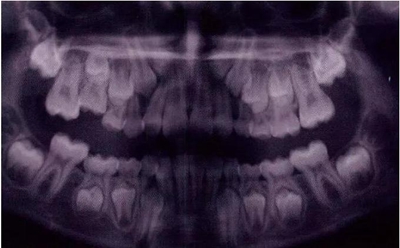

圖11是一張曲面體層片,上面顯示了一名九歲男孩同時(shí)患有55,75,和85的下沉。其55和85 為中度下沉,75為輕度下沉。這幾顆牙都沒有齲齒,都伴有恒牙胚的存在,并且沒有鄰牙傾斜和間隙喪失的臨床表現(xiàn)。給予這個(gè)孩子的方案是醫(yī)囑三個(gè)月常規(guī)復(fù)診以觀察監(jiān)測(cè)這些牙的下沉情況。結(jié)果這些牙均未加重至超過中度下沉,并且全部自然脫落,恒牙正常萌出。

圖11:曲面體層片顯示一名9歲男孩乳磨牙下沉,繼承恒牙胚存在。